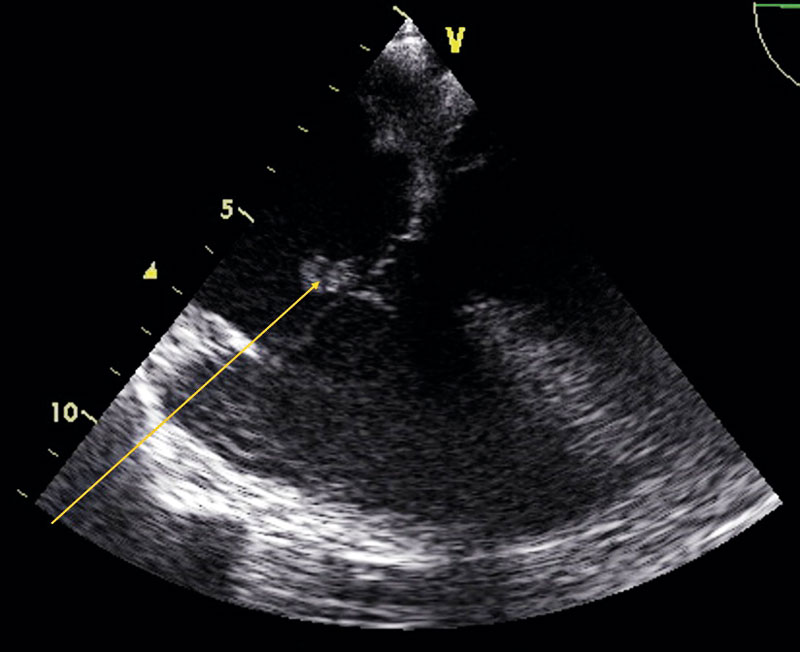

Transesofagal långaxelvy: aortarotabscess.